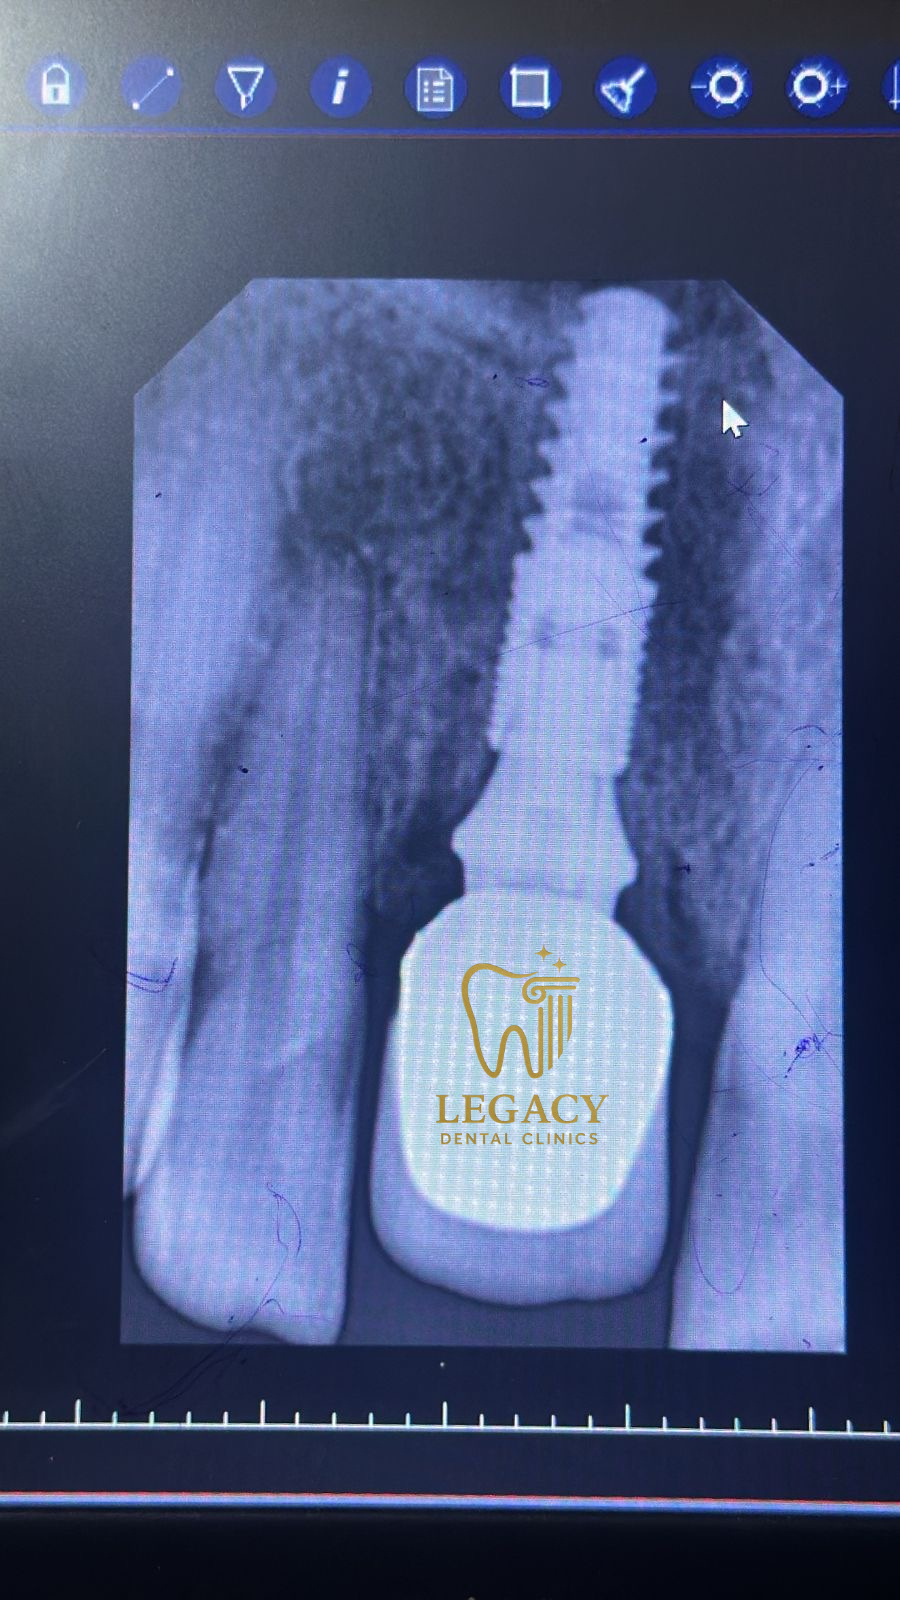

حالة زراعة فورية لسن أمامي - د.عمر نافوخ